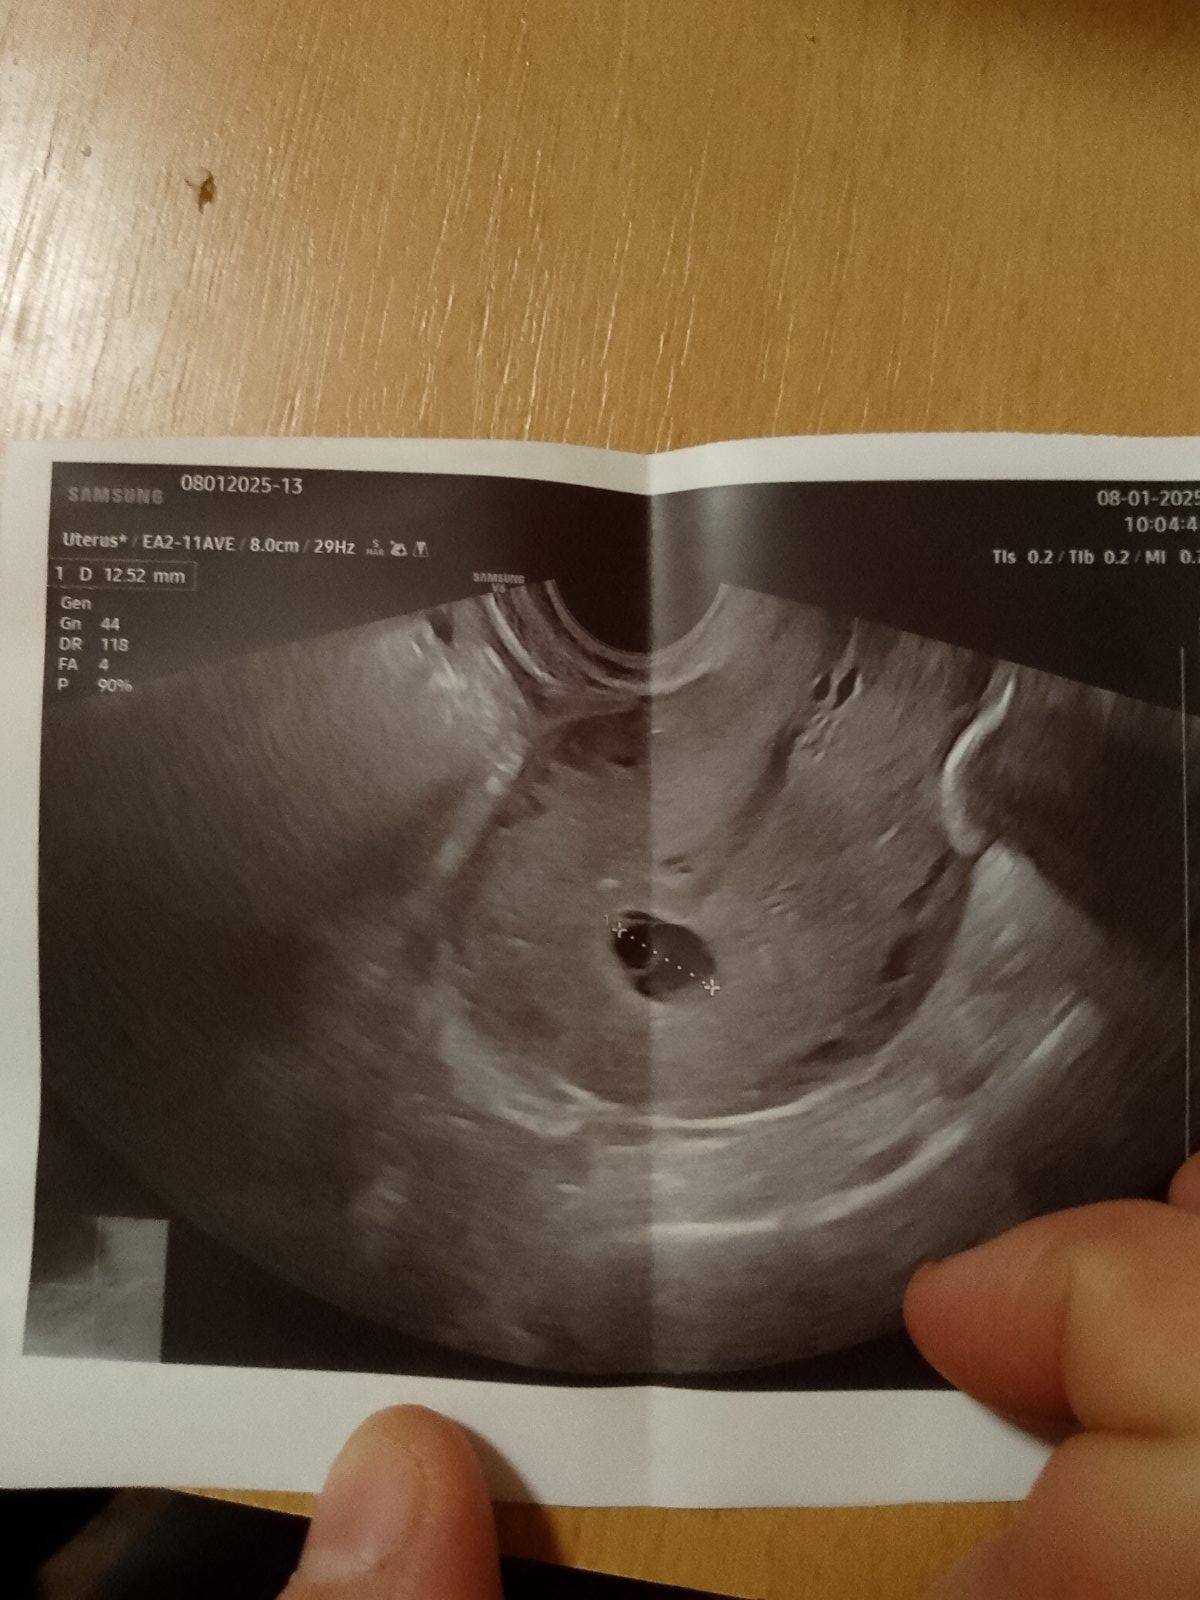

Ahoj, včera jsem byla na kontrole, vycházelo to na 6+6. Doktor mi řekl, že plodový váček podle posledních měsíčku sedí. Kdyby bylo něco špatně,tak by mi to určitě řekl. Ale na ultrazvuku nebyl zatim vidět plod. Měl to někdo taky takhle? Že zatim nebylo nic vidět, až při další kontrole?

Přikládám foto ultrazvuku. Děkuji za názory🙂